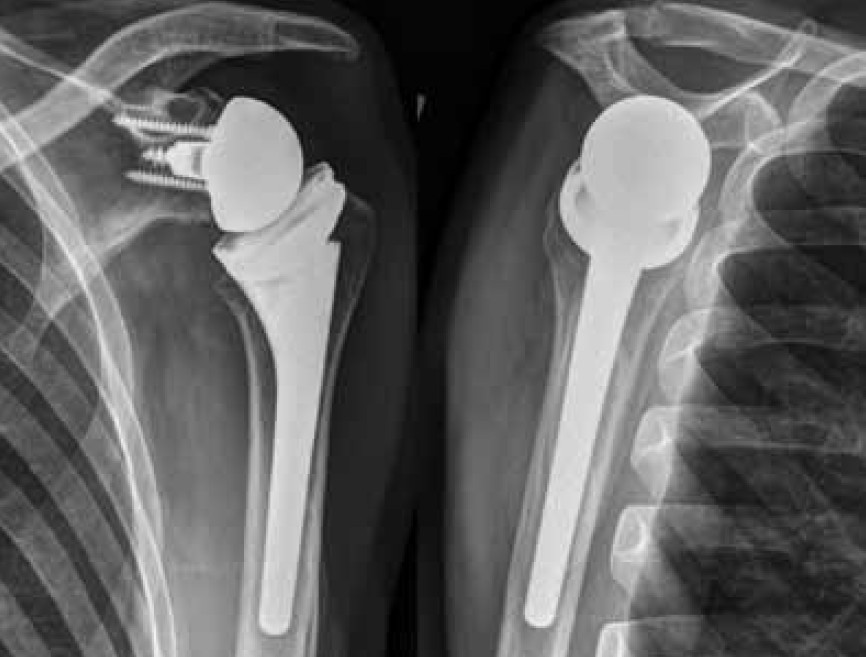

Irreparable Rupturen der Rotatorenmanschette

Ein Überblick über die aktuellen Therapieoptionen MÜNCHEN - Die operative Behandlung der nicht rekonstruierbaren Rotatorenmanschetten-Läsion stellt eine Herausforderung für den behandelnden Orthopäden dar. Allerdings stehen heute ausgezeichnete arthroskopische und offene Möglichkeiten zur Verfügung, die jeweils individuell auf die exakte Pathologie und den Anspruch des Patienten abgestimmt werden müssen. Bei korrekter Indikationsstellung und exakter Patientenselektion [...]